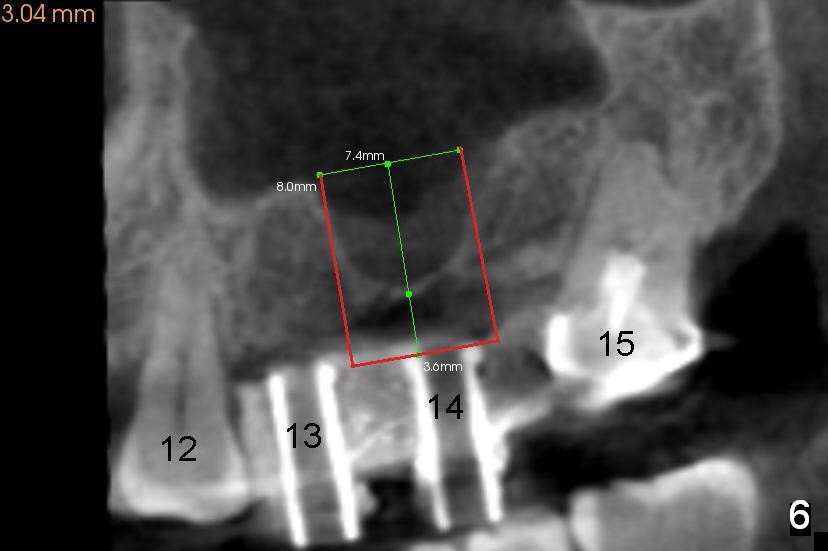

After crestal incision, a 3.5 or 4 mm trephine bur is used for 2 mm at #14. The regional sinus floor is lifted using a Bicon flat-end osteotome, followed by bone graft and taps. If the 6x11 mm tapered tap does not gain stability (Fig.3), use either 6x11 mm round tap (Fig.4) or 7 or 8x11 mm tapered tap (Fig.5). If the last does not work, try a larger round tap (Fig.6). In all, the sinus floor is pushed upstairs and an implant is inserted to be engaged into the sides of the sinus floor (Fig.7).

Coronally, a round implant does not appear to obtain more bone contact than a tapered one of the same diameter (Fig.8,10). Internal sinus lift works for this case?